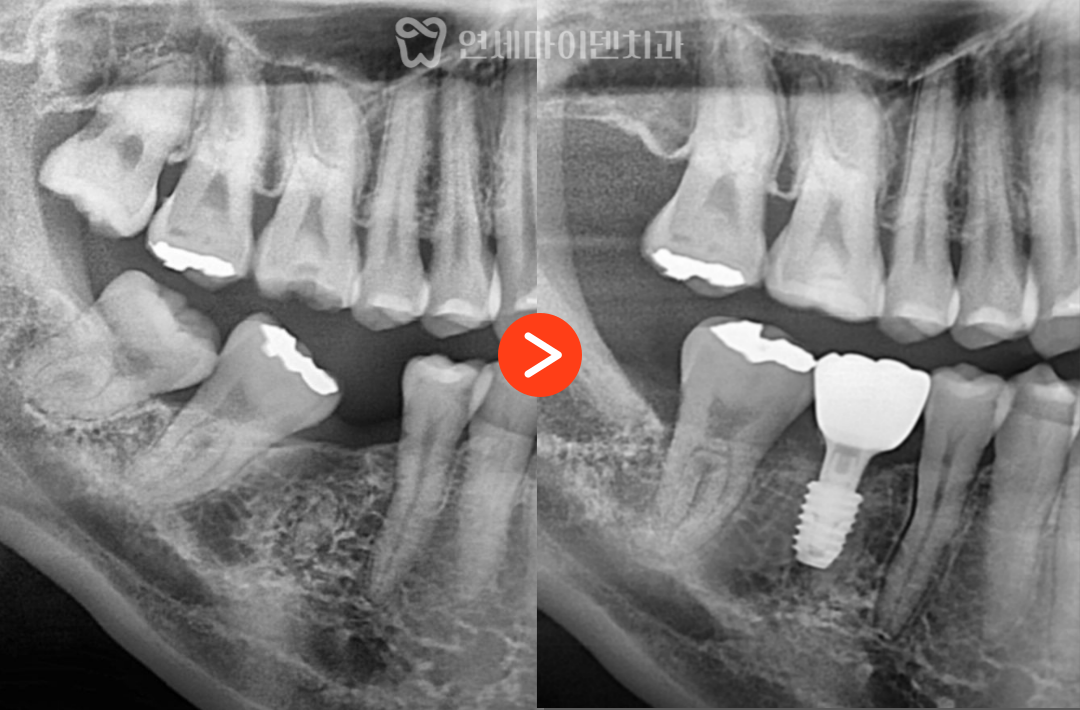

해당 환자분은 오른쪽 아래 6번 어금니를

오래전에 발치하신 분으로,

그 결과 뒤쪽의 7번 어금니와 8번 사랑니가

앞으로 기울어져 있었습니다.

이로 인해 임플란트를 식립할 공간이 부족한 상태였고,

보철만으로는 치료가 불가능했습니다.

임플란트 식립

공간 확보 후에는 6번 어금니 부위에 임플란트를 식립하였고,

약 2~3개월간의 안정화 기간을 거쳐

뼈와 임플란트가 단단히 결합되었습니다.

- 임플란트 크라운이 완성되었고,

- 교합과 주변 치아의 움직임 없이 안정적인 결과를 얻을 수 있었습니다.